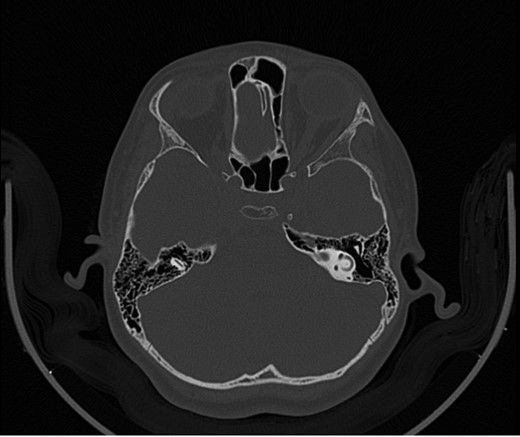

A 14-year-old male patient presented to the ENT clinic with bilateral hearing loss with no other otolaryngological symptoms. History from the patient stated a road traffic accident (RTA) 12 months ago. Meanwhile, the patient had no hearing problems prior to the RTA. Furthermore, detailed history of the accident revealed that the patient had no apparent skull injuries while pure tone audiometry (PTA) on presentation revealed bilateral conductive hearing loss and auditory brainstem response revealed right mild hearing loss and left moderate hearing loss. As a result, he was fitted with hearing aid for four months after presentation and was not compliant to it on the long-term. The patient is a non-smoker and is medically free with normal developmental milestones and negative family history of hearing complaints. Local examination of the ear revealed intact but minimally retracted tympanic membrane bilaterally. PTA was done in 2014 revealed right mild to moderate mixed hearing loss and conductive hearing loss at low frequency (Table 1). Meanwhile, the left ear had mild to moderate sensory hearing loss at high frequency (Table 2). The speech audiogram results show equal canal volume in both ears, less tympanometry pressure on the right ear and less compliance on the right ear (Table 3). The CT showed that both ossicular chains are deranged, and bilateral abnormal ossicles with no fracture or mass (Figures 1–3).

Figure 3:

CT mastoid, deranged left side ossicular disruption.